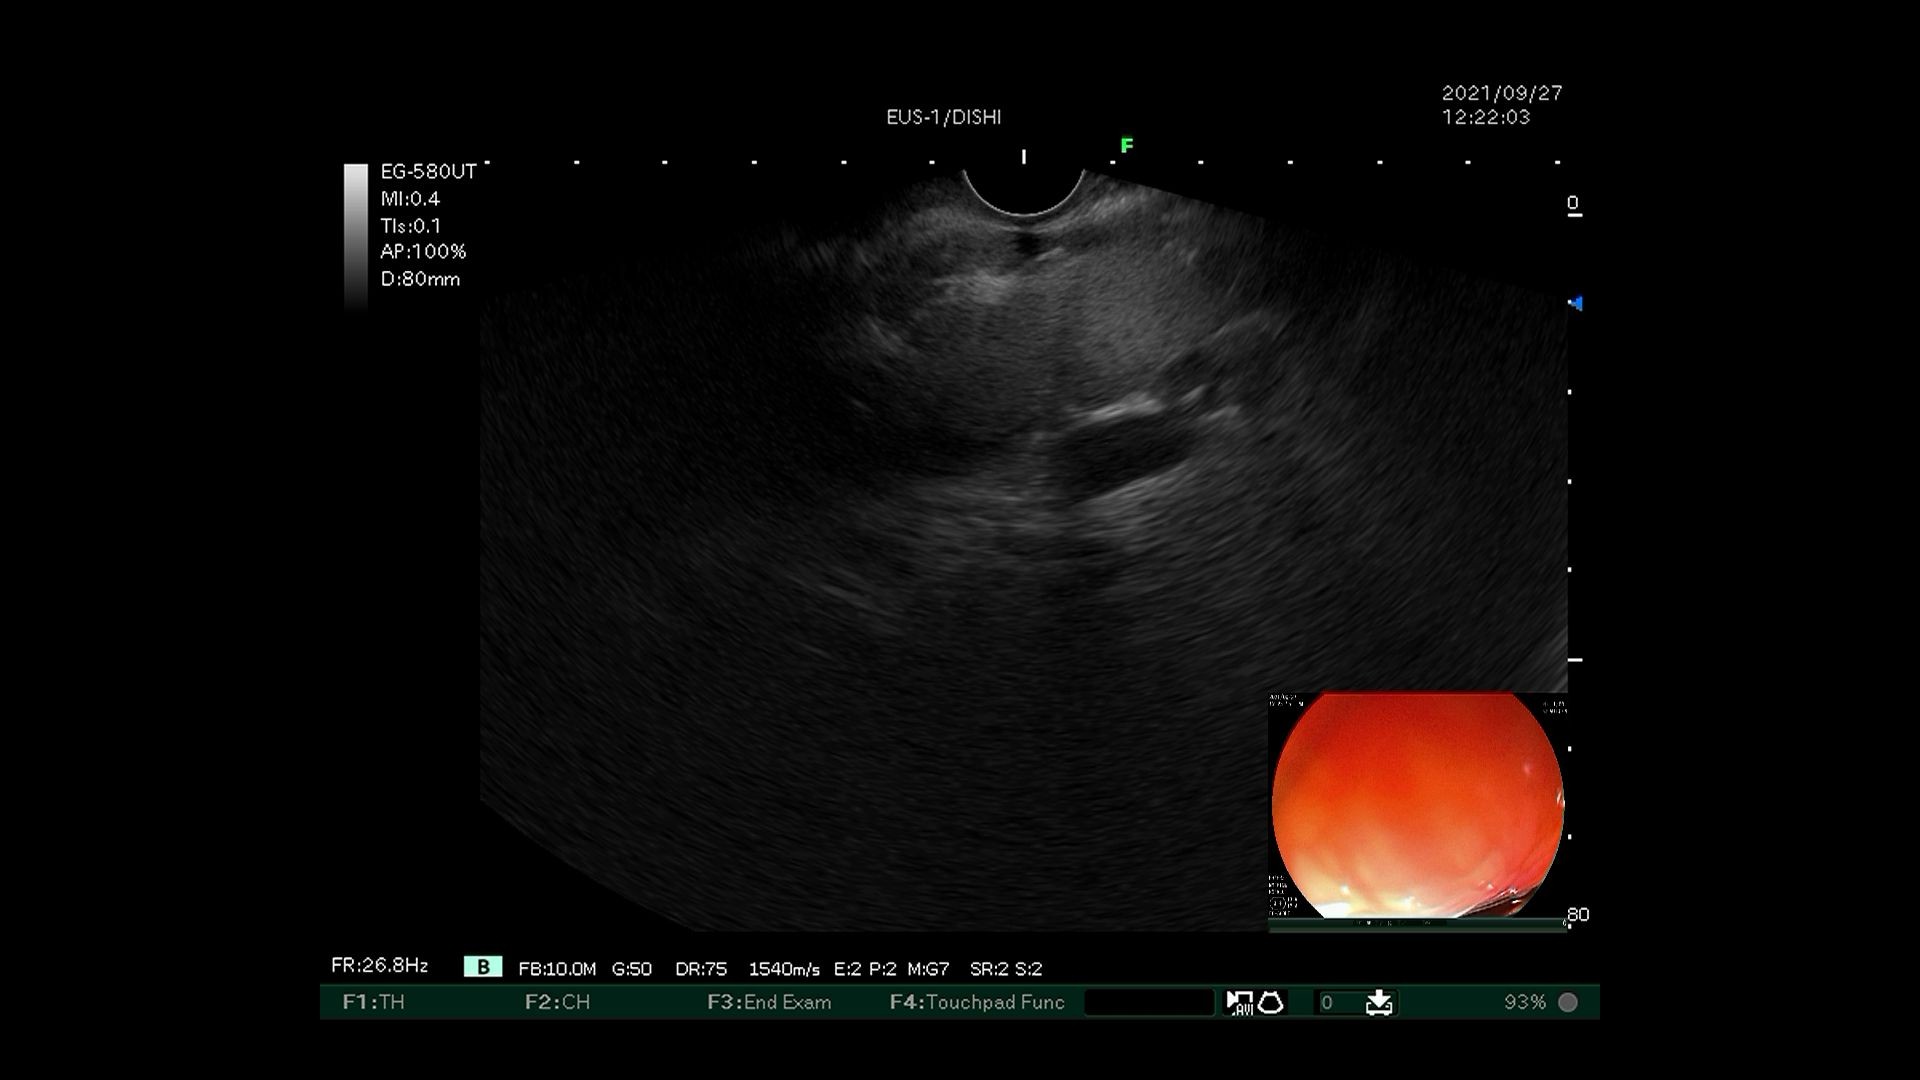

5)拔出针芯,三明治法行组织胶注射。

超声内镜引导下弹簧圈置入联合组织胶栓塞术先使用超声内镜识别胃底曲张静脉,选取曲张静脉内径最宽处,在超声内镜引导下经食管下段、膈肌角以19G穿刺针穿入曲张静脉,置入数枚略大于曲张静脉内径的弹簧圈,然后用“高糖-组织胶-高糖”三明治法于曲张静脉内注射组织胶,最后使用超声内镜确认曲张静脉血流信号消失。该技术可明显降低异位栓塞的风险,但需要手术者同时具有超声内镜及静脉曲张两个亚专业的熟练操作技巧,手术大出血风险极高,若有不慎即可导致术中患者死亡。